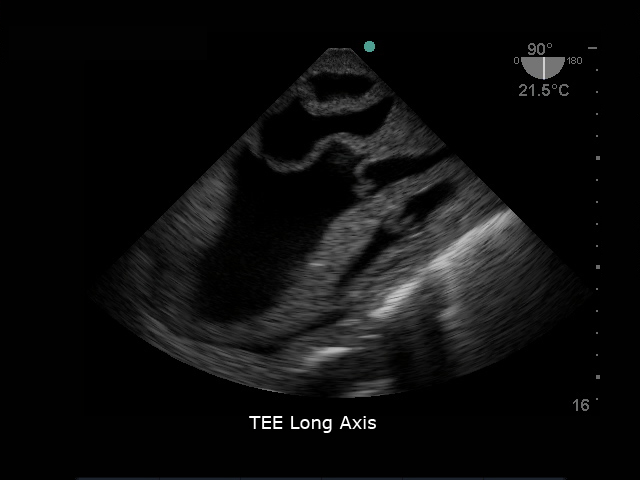

模型具有逼真的心脏解剖超声图像,从不同角度可进行经食道和经胸廓心脏20个标准切面探查及测量,同时可进行超声引导下心包穿刺的完整流程训练。